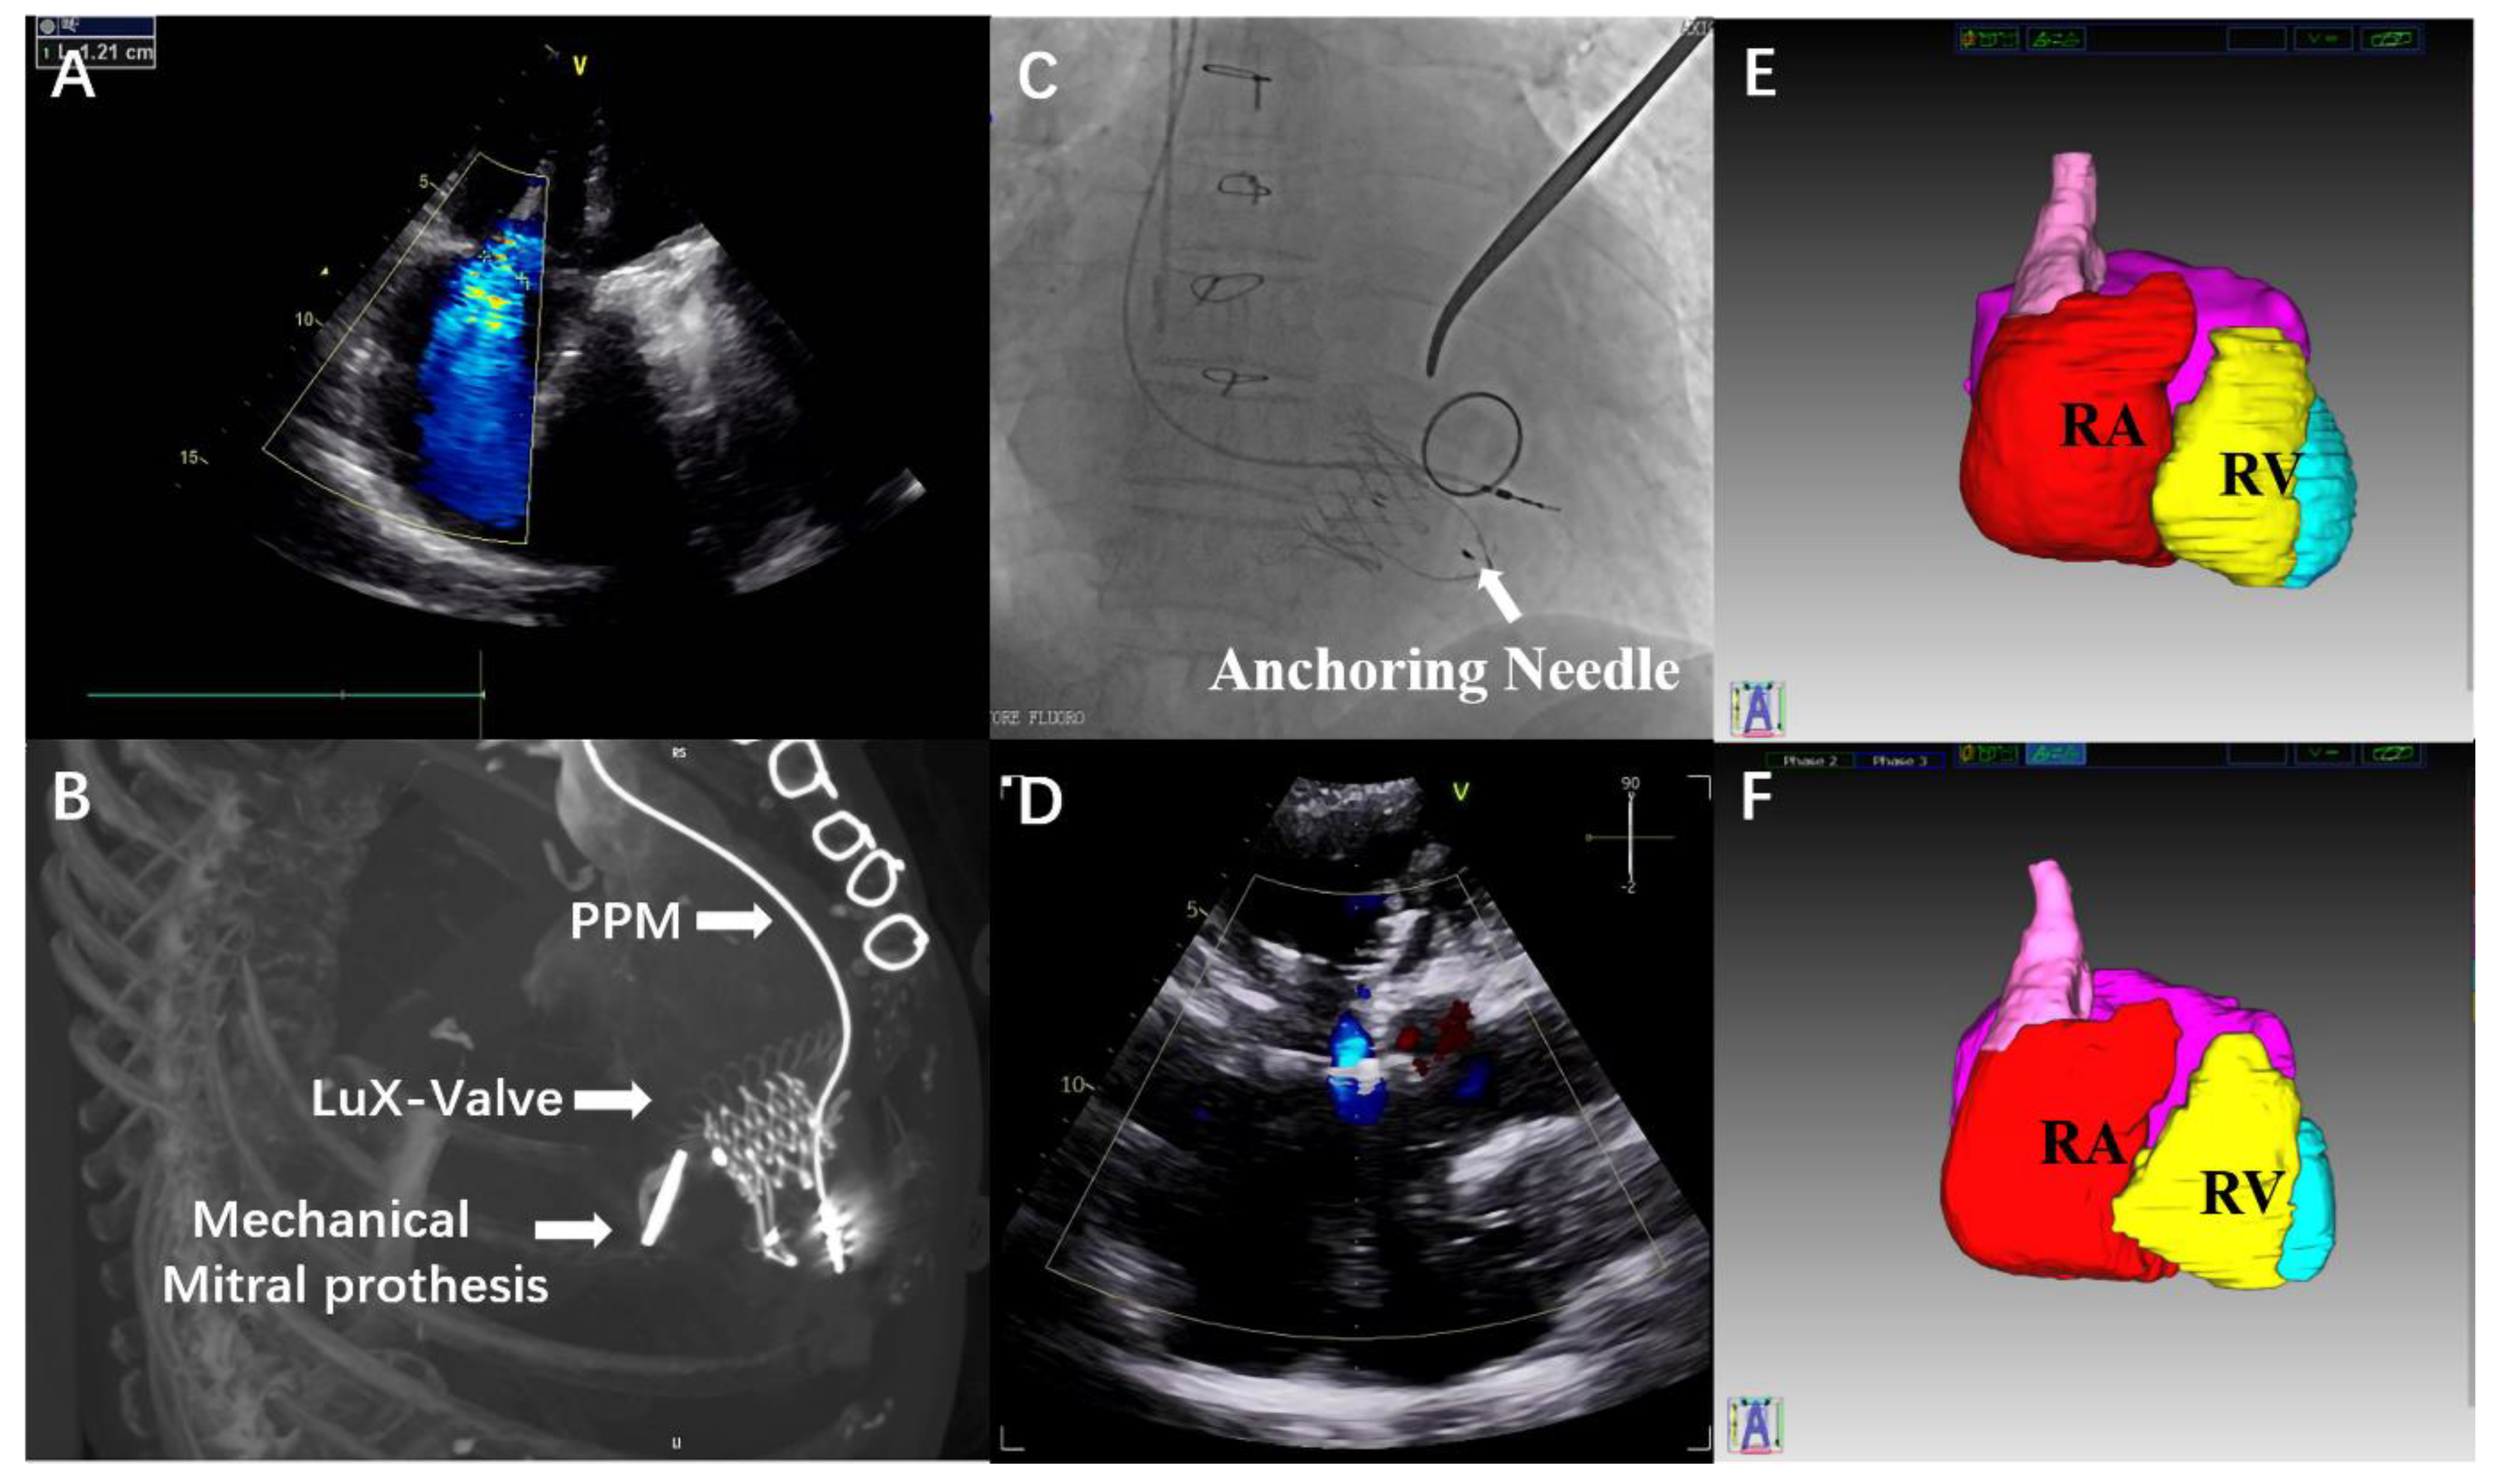

4-Year Follow-Up after Transatrial Transcatheter Tricuspid Valve Replacement with the LuX-Valve

2. Case Report